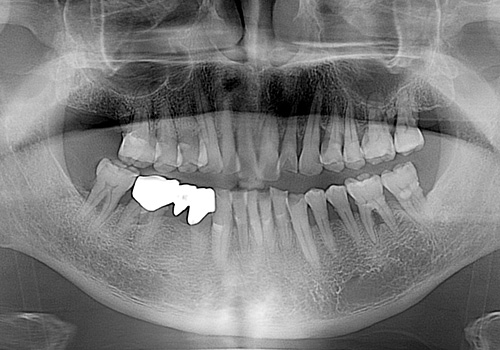

김○두님 임플란트 식립 전

2017년 7월

김○두님 임플란트 식립 후

2020년 6월 -